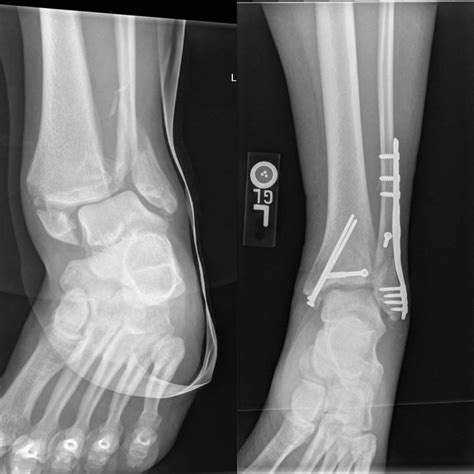

Understanding the intricacies of an Xray of broken bones is crucial for both medical professionals and patients. This diagnostic tool plays a pivotal role in identifying fractures, assessing their severity, and planning appropriate treatment. Whether you are a healthcare provider or someone who has experienced a bone injury, grasping the fundamentals of X-ray imaging can provide valuable insights into the healing process and overall recovery.

When a bone is fractured, the continuity of the bone is disrupted, creating visible gaps or misalignments on the X-ray image. These disruptions can range from simple cracks to complex fractures involving multiple bone fragments. The Xray of broken bones helps medical professionals determine the type and extent of the fracture, which is essential for developing an effective treatment plan.

• Surgery: In cases of complex or displaced fractures, surgical intervention may be required to realign the bone fragments.

Interpreting an Xray of broken bones requires a trained eye and a thorough understanding of bone anatomy. Radiologists look for specific signs of fractures, including:

• Discontinuity of the Bone: Visible gaps or breaks in the bone structure.

• Misalignment: Bones that are not properly aligned, indicating a fracture.

• Overlapping Fragments: Bone fragments that overlap, suggesting a comminuted fracture.

• Soft Tissue Swelling: Swelling around the fracture site, which can indicate the severity of the injury.